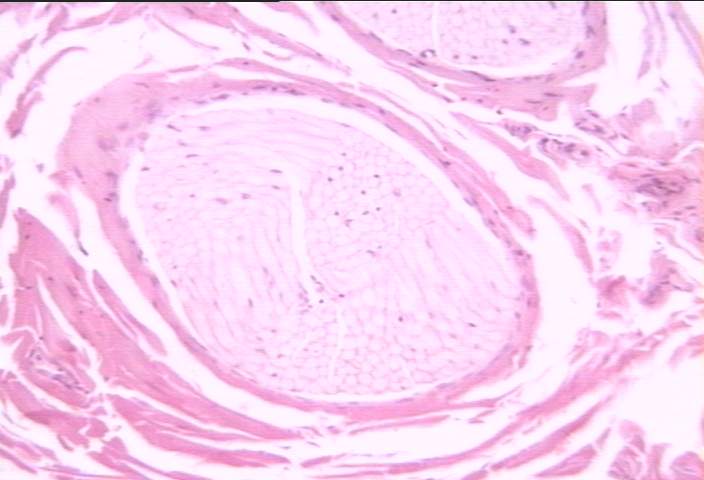

切片位置:神經 (nerve)

切片倍率:100x

染色方式:h&e stain

中倍率 (100x) 下常規染色之神經橫切,可見外圍有結締組織 (endoneurium) 而排列呈束狀之神經纖維 (nerve fibers)。神經纖維一般呈現淡染色,其間之細胞核j為許旺氏細胞 (schwann cells) 之細胞核。